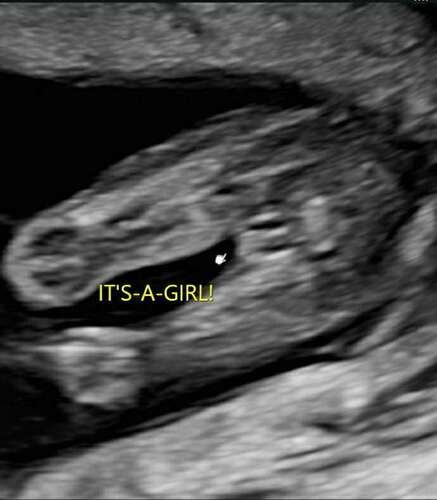

Met 15+2 een geslachtsbepaling echo laten doen en als verassing gelaten tot thuis, het is een meisje 🩷 Bij de 20 weken zelf kunnen kijken en zag toen erg duidelijk dat het geen jongetje is. Bij de laatste echo met 33 weken nog even dubbel check en is nog steeds een meisje! Ik moet nog zo'n 6 weken dus 100% weet ik het nog steeds niet 😜